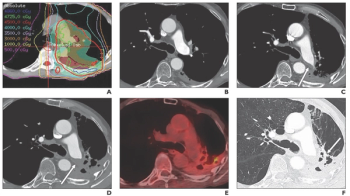

Research indicates patients who undergo a single 28-Gy session experience similar outcomes to those who have four 12-Gy sessions, pointing to safer, faster treatment.